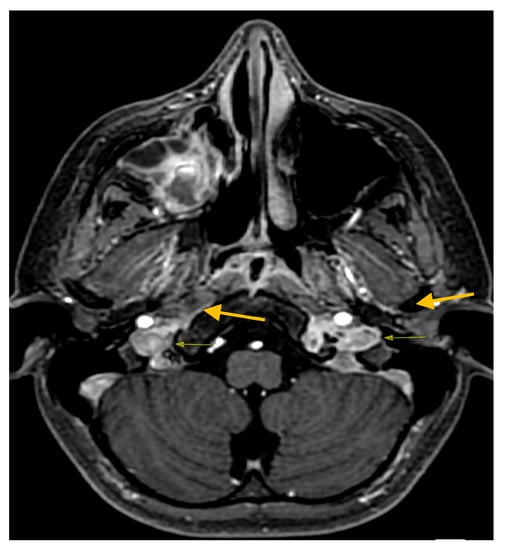

2. Case Report